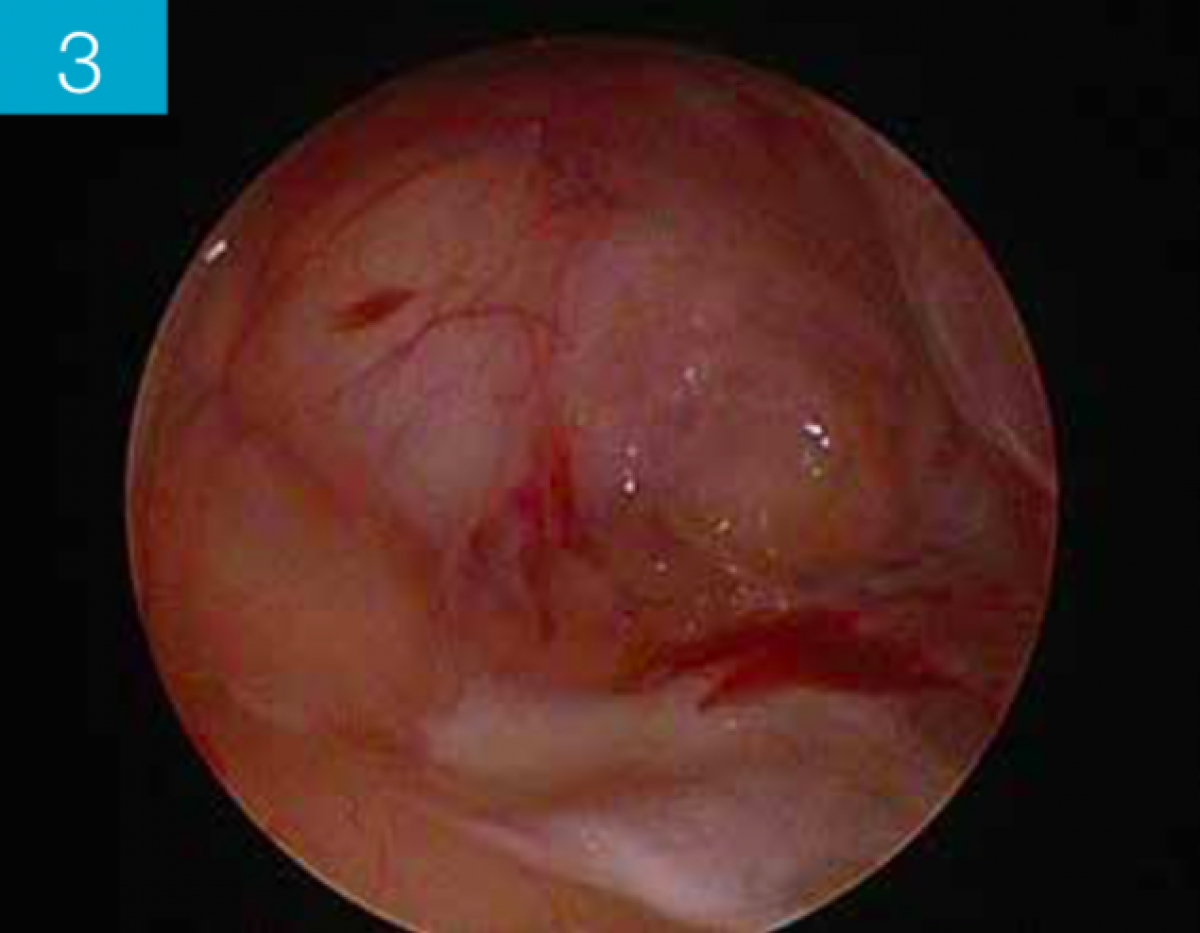

Once the caries was removed, the finishing stage of the cervical step and the buccal and palatal margins of the tooth in question was performed. The resulting cavity is sufficient to properly carry out a restoration with easily refinable and polished edges. At this point the FenderWedge was removed, the adhesive procedures were completed, taking care to protect the adjacent teeth and a second wedge was inserted. The FenderMate (Directa) is equipped with a sectional matrix which in this case perfectly adapts to the cavity design without having to apply an additional separator ring as in traditional sectional matrix systems.      (Figure 3,4)